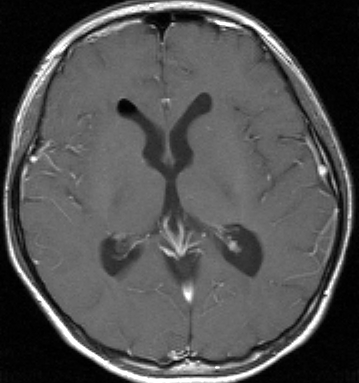

思春期の女の子にできた小脳腫瘍です。とても大きく見えますがほとんどが水たまり(のう胞といいます)。第4脳室が腫瘍で圧迫されて閉塞性水頭症になりました。のう胞の中に出血がありますが毛様細胞性星細胞腫では腫瘍内出血をしばしば見ます。右の写真で脳室が大きくなっています。こんなに大きいのに小脳症状は全くなくて,頭痛と嘔吐が症状でした。

手術後のMRIです。水頭症も改善してますから症状も消失しましたし,すぐに退院です o(^o^)o